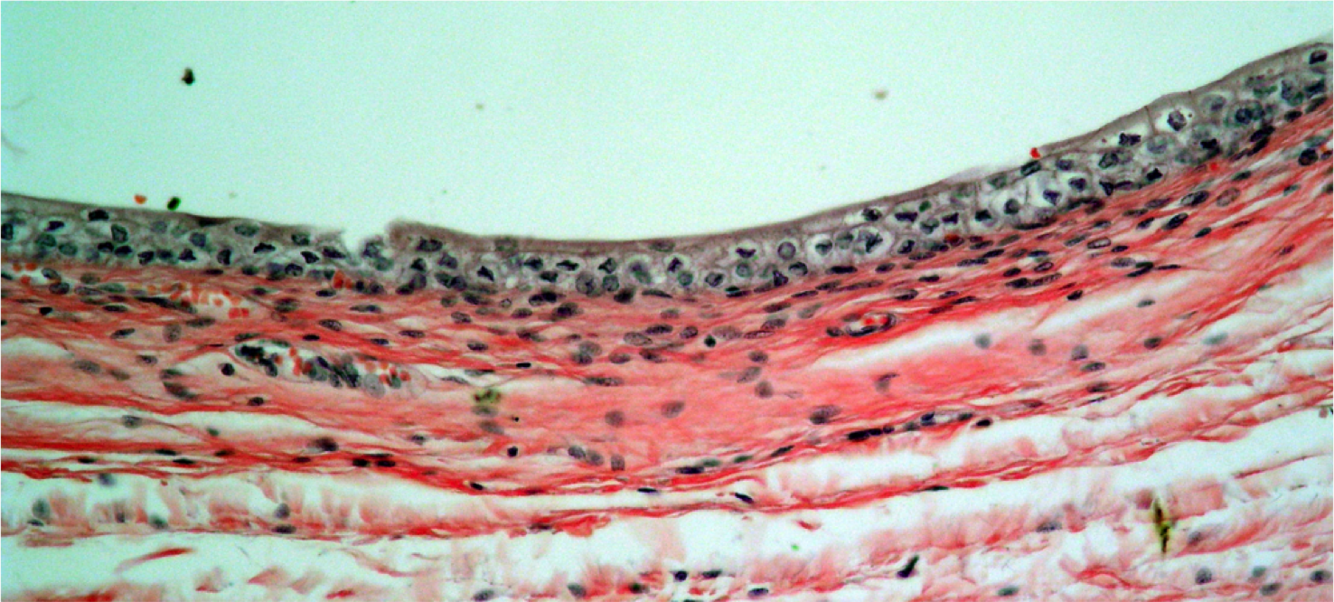

Identify

Pseudostratified Columnar Ciliated Epithelium from Human Trachea

Goblet cells, ciliated cells, lymphocytes (black dots), basal bodies (dark pink line at base of cilia)

Thick basement membrane